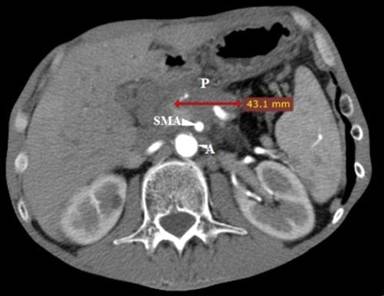

A forty-eight-year-old, male patient with significant weight loss and dyspepsia underwent diagnostic CT scan in July 2011 which revealed a tumor mass in the body of the pancreas. The tumor was histologically verified as an adenocarcinoma. It was inoperable at the time of diagnosis due to infiltration of the hepatic artery, the splenic artery and the superior mesenteric artery (Figure 1). A cycle of combined chemotherapy applications started in August 2011 and continued to December 2012. Gemcitabine (1,600 mg/m2 i.v. weekly) plus ambulatory (Erlotinib 100 mg/day p.o.) were administered in these seventeen months. Control CT scans and the evaluation of the tumor-response showed stabilization of the disease during this period.

Figure 1. Contrast enhanced CT scan at the time of diagnosis. A: aorta; P: pancreatic lesion; SMA: superior mesenteric artery |